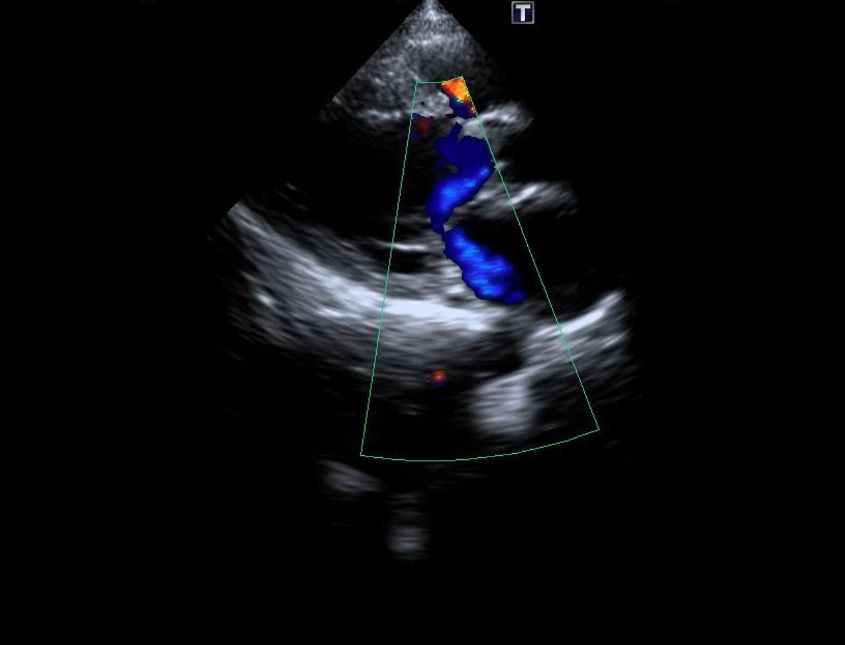

We chose an appropriately sized occluder, which was 20% greater than the entrance diameter of the ruptured SVA. The selected occluder with its attached delivery cable was inserted through the delivery sheath from the venous route, and its aortic disc was deployed in the ascending aorta. Positioning of the device (an ADO single-disc device of 6-8 mm) was then confirmed under transthoracic echocardiography (Figures 4A-C, Videos 4A-C).

Figure 4. (A) Positioning of the Amplatzer Duct Occluder (ADO) device (Abbott) (blue arrow). (B) Transthoracic echocardiography. (C) No residual shunt observed across the defect following device placement on transthoracic echocardiography.

(Figure 4B)